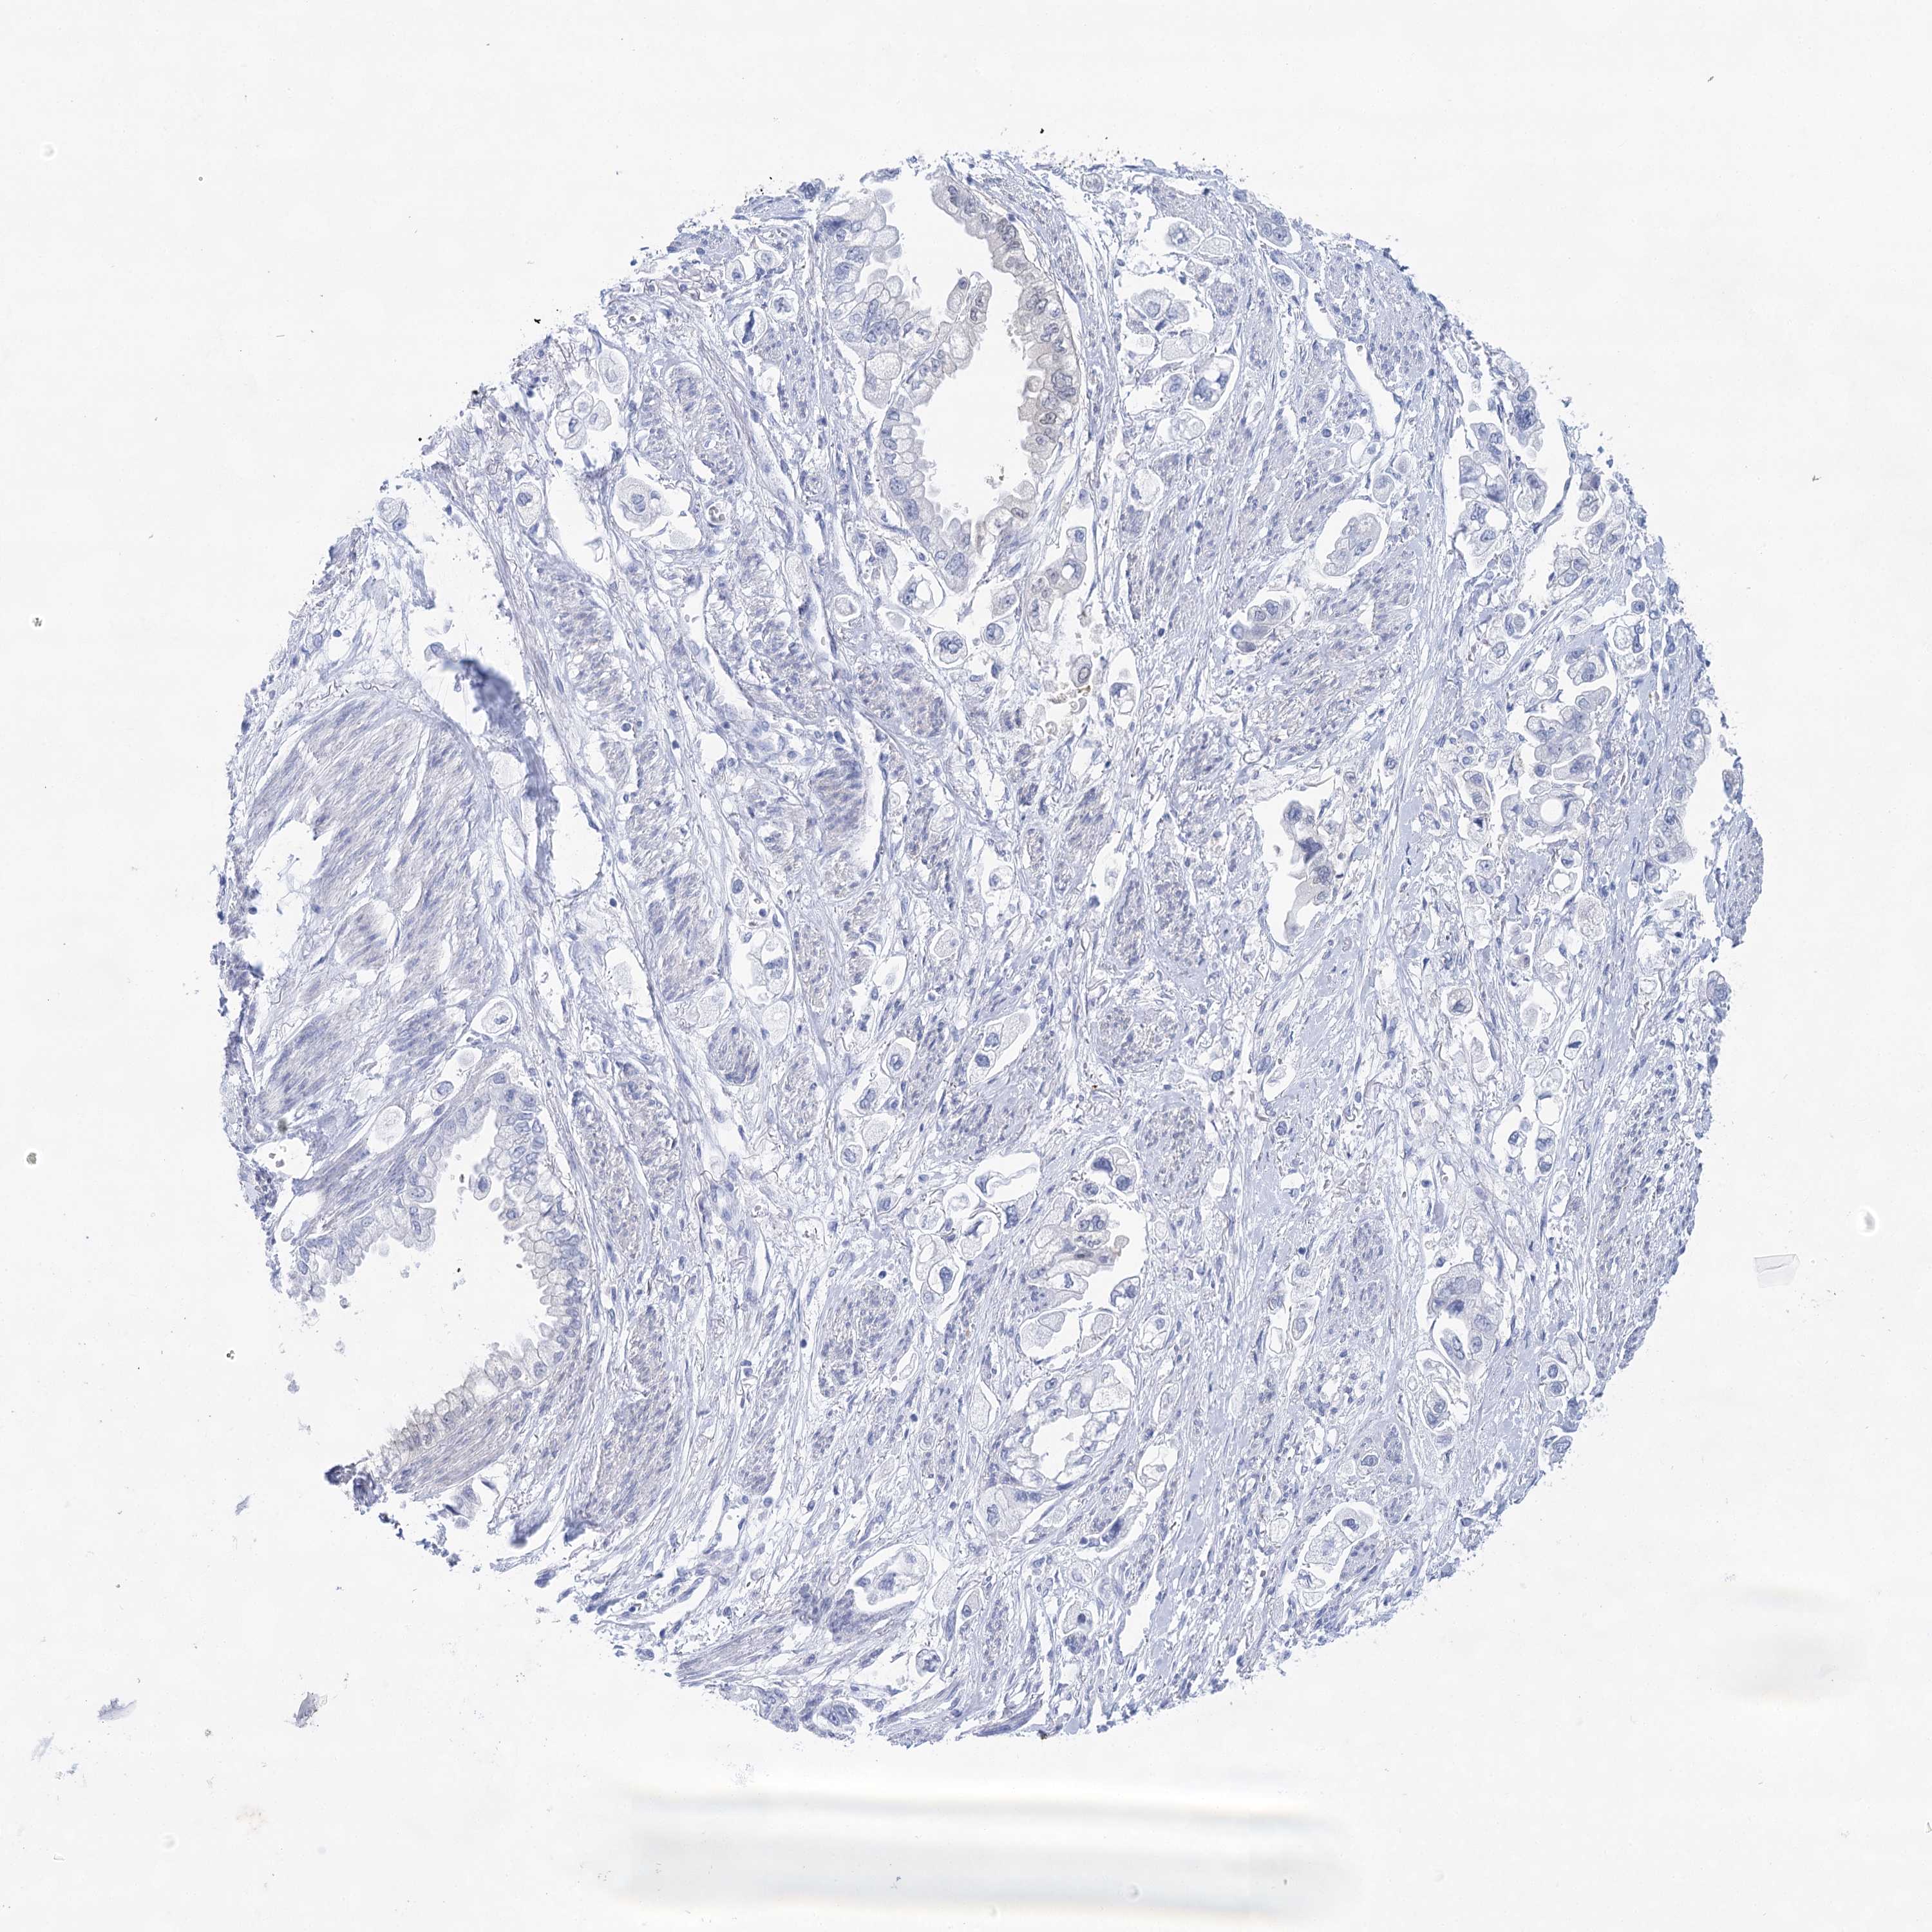

STOMACH CANCER - Protein expressioni

A mouse-over function shows sample information and annotation data. Click on an image to view it in a full screen mode. Samples can be filtered based on level of antibody staining by selecting one or several of the following categories: high, medium, low and not detected. The assay and annotation is described here.

Note that samples used for immunohistochemistry by the Human Protein Atlas do not correspond to samples in the TCGA dataset.

Antibody stainingi

Antibody staining in the annotated cell types in the current human tissue is reported as not detected, low, medium, or high, based on conventional immunohistochemistry profiling in selected tissues. This score is based on the combination of the staining intensity and fraction of stained cells.

Each image is clickable and will lead to virtual microscopy that enables deeper exploration of all samples and also displays staining intensity scores, fraction scores and subcellular localization as well as patient and tissue information for each sample.

Antibody HPA029855

Antibody HPA029856

Antibody CAB026343

Staining

High

Medium

Low

Not detected

Intensity

Strong

Moderate

Weak

Negative

Quantity

>75%

75%-25%

<25%

None

Location

Nuclear

Cytoplasmic/membranous

Cytoplasmic/membranous,nuclear

Adenocarcinoma, NOS